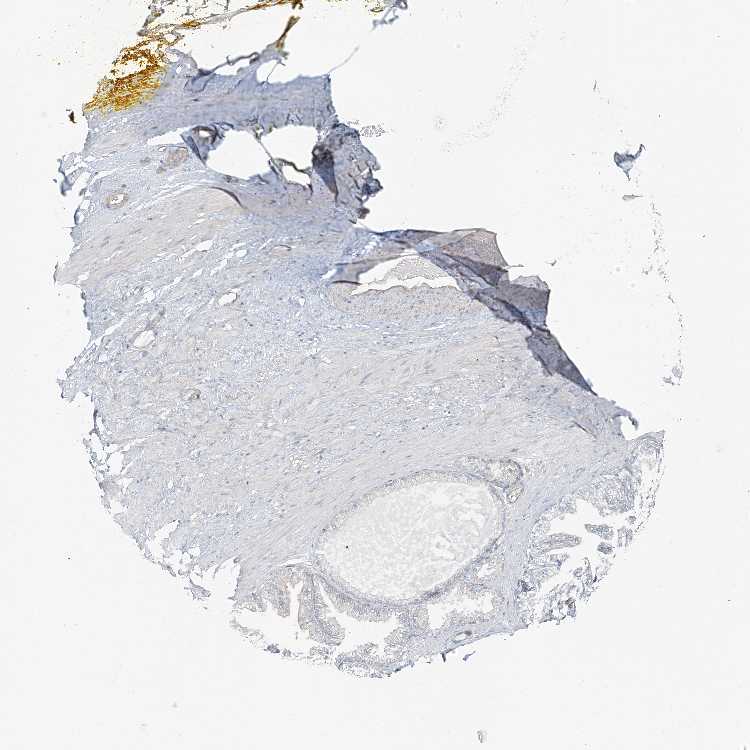

SOFT TISSUE 1 - Antibody stainingi

Antibody staining in the annotated cell types in the current human tissue is reported as not detected, low, medium, or high, based on conventional immunohistochemistry profiling in selected tissues. This score is based on the combination of the staining intensity and fraction of stained cells.

Each image is clickable and will lead to virtual microscopy that enables deeper exploration of all samples and also displays staining intensity scores, fraction scores and subcellular localization as well as patient and tissue information for each sample.

Antibody HPA034659

Fibroblasts Not detected